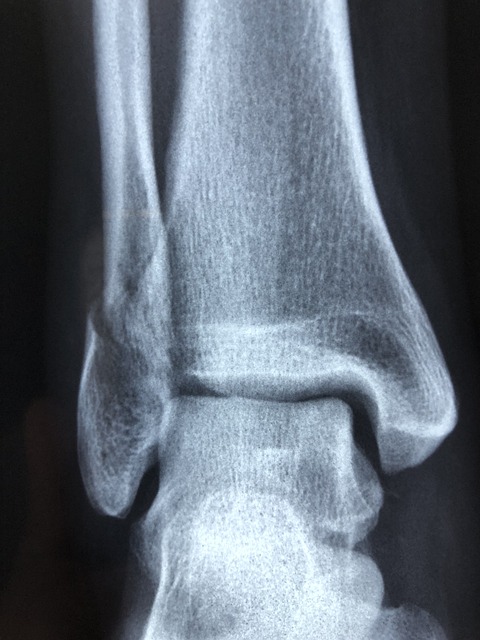

발목 염좌는 발목 관절이 정상적인 운동 범위를 넘어 비틀리면서 발생하는 흔한 부상입니다. 이는 달리기, 점프, 스포츠와 같은 신체 활동뿐만 아니라 고르지 않은 표면을 걷거나 부적절한 신발을 신는 등 일상적인 상황에서도 발생할 수 있습니다. 이러한 움직임으로 인해 발목을 지지하는 인대가 늘어나거나 찢어지면 발목 염좌가 발생하게 됩니다.

염좌의 심각도는 인대 손상 정도에 따라 달라지며 경증, 중등도, 중증의 세 가지 등급으로 분류됩니다. 가벼운 발목 염좌에서는 인대가 최소한으로 늘어나거나 찢어져 발목 관절 주위에 약간의 불편함, 압통 및 부기가 발생합니다. 개인은 약간의 통증과 뻣뻣함을 경험할 수 있지만 여전히 영향을 받은 발목으로 걷고 체중을 지탱할 수 있습니다.

중등도 발목 염좌는 인대가 더 심하게 늘어나거나 부분적으로 찢어져 발목 주위에 중등도의 통증, 부기 및 멍이 발생합니다. 걷는 것이 더 어려워지고, 개인은 절뚝거리거나 영향을 받은 발목에 체중을 싣는 데 어려움이 있으며, 운동범위가 감소합니다. 심한 발목 염좌는 인대가 완전히 찢어지거나 파열되어 심한 통증, 부종, 멍이 발생하는 경우 발생합니다. 개인은 영향을 받은 발목에 체중을 지탱할 수 없으며 관절에 심각한 불안정성을 경험할 수 있습니다. 어떤 경우에는 부상 당시 눈에 보이는 변형이나 "터지는" 느낌이 있을 수 있습니다.